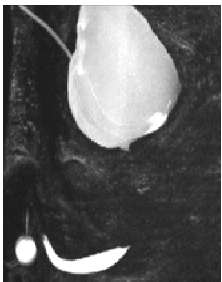

Magnetic Resonance Imaging (MRI) in Pelvic Fracture Urethral Injuries to Evaluate Urethral Gap: A Protocol Based Study

Pankaj M Joshi1*, Devang J Desai1, Devashree Joshi2, Darshan Shah3, Ashish Atre3, Unmesh Bhosale3,Yogeshwari Deshmukh3,Sandesh Surana1, Hazem Orabi1,Subramanian Iyer1,Sanjay B Kulkarni1